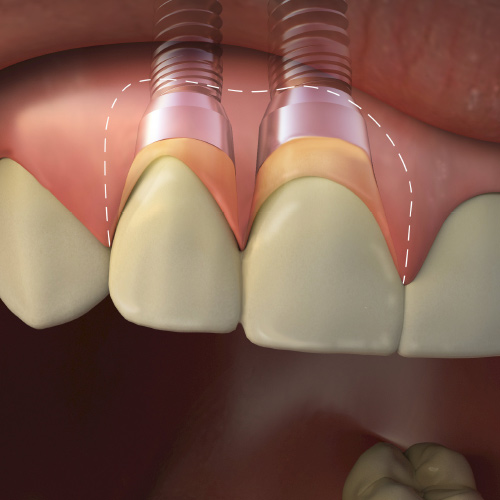

Implantology Updates

This Compendium eBook features a continuing education (CE) article on hard- and soft-tissue augmentation for implant therapy in the esthetic zone. This eBook also includes a case report article on a minimally invasive technique for the reconstruction of class III sockets with simultaneous i...

Implantology Advances

This Compendium eBook offers a continuing education (CE) article on partial extraction therapy in implant dentistry, with an emphasis on the biologic and anatomic conditions necessary for optimal outcomes with implant surgery. This eBook also includes a case report describing a strategy for...

A Comprehensive Approach to Plan and Design the Emergence Profile Around Dental Implants

This Compendium eBook features a continuing education (CE) article that discusses the design and strategic development of the emergence profile of restorations. This article examines the most important aspects of the creation of an emergence profile, with a focus on developing strategies th...